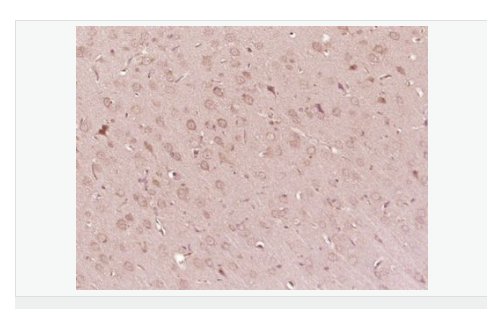

IHC-P,

| 产品应用 | WB=1:500-2000 ELISA=1:5000-10000 IHC-P=1:100-500 IHC-F=1:100-500 IF=1:100-500 (石蜡切片需做抗原修复) not yet tested in other applications. optimal dilutions/concentrations should be determined by the end user. |

| 产品介绍 | ATP7b is an important protein for copper transport and elimination of excess copper from the body. ATP7b transports metals in and out of cells using ATP. There are 3 known isoforms of the ATP7b gene; A is found in the liver, kidney, and brain, the shorter form B is found in brain tissue, and the third isoform, known as WND/140 KDA is found in mitochondria. Mutations in the ATP7b gene can cause Wilson's disease, an inherited disorder causing copper poisoning in the brain and liver. Function: Involved in the export of copper out of the cells, such as the efflux of hepatic copper into the bile. Subunit: Monomer. Interacts with COMMD1/MURR1. Subcellular Location: Golgi apparatus, trans-Golgi network membrane; Multi-pass membrane protein. Isoform 2: Cytoplasm. WND/140 kDa: Mitochondrion. Tissue Specificity: Most abundant in liver and kidney and also found in brain. Isoform 2 is expressed in brain but not in liver. The cleaved form WND/140 kDa is found in liver cell lines and other tissues. Post-translational modifications: Isoform 1 may be proteolytically cleaved at the N-terminus to produce the WND/140 kDa form. DISEASE: Defects in ATP7B are the cause of Wilson disease (WD) [MIM:277900]. WD is an autosomal recessive disorder of copper metabolism in which copper cannot be incorporated into ceruloplasmin in liver, and cannot be excreted from the liver into the bile. Copper accumulates in the liver and subsequently in the brain and kidney. The disease is characterized by neurologic manifestations and signs of cirrhosis. Similarity: Belongs to the cation transport ATPase (P-type) (TC 3.A.3) family. Type IB subfamily. Contains 6 HMA domains. SWISS: P35670 Gene ID: 540 Database links: Entrez Gene: 540 Human Omim: 606882 Human SwissProt: P35670 Human Unigene: 492280 Human Important Note: This product as supplied is intended for research use only, not for use in human, therapeutic or diagnostic applications. 铜转运蛋白质β链是铜转运蛋白质家族中的一种,可调节细胞内铜离子水平的铜转运P型三磷酸腺苷酶,ATP7B是生物体内广泛存在的一种极为重要的细胞膜上的酶,它的功能主要是维持细胞内外的离子及渗透压平衡、跨膜电化学和细胞的能量代谢. |